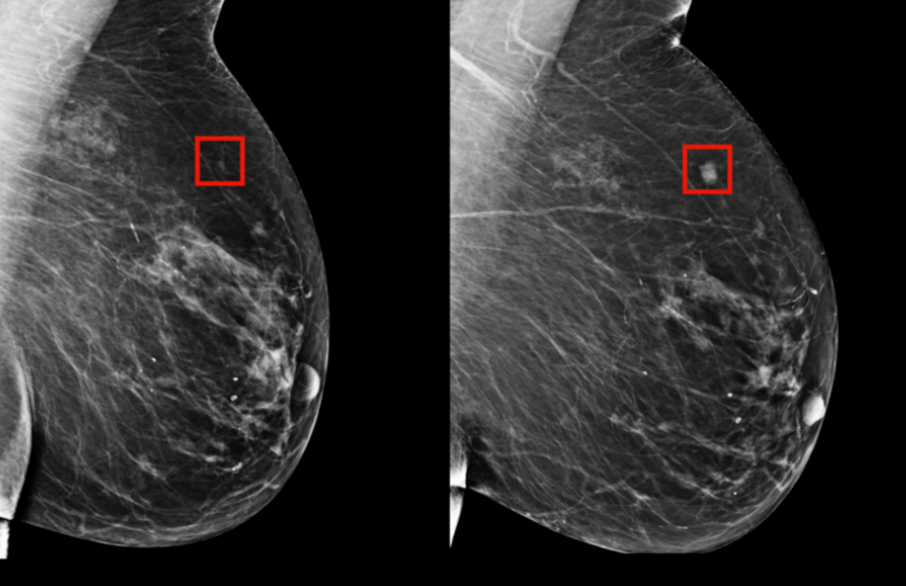

早发现、早诊断,是提高乳腺癌疗效的关键所在。当下对乳腺癌的检测包括乳腺 X 线摄影、超声(US),必要时则进行乳腺磁共振检查(MRI)。

乳腺 X 线摄影

乳腺 X 线摄影是近年来国际上推荐的乳腺癌筛查中的主要方法,这种方法较适用于乳腺密度相对较低的女性,而乳腺超声则相对比较适合于致密性乳腺。

亚洲女性的乳腺密度相对致密,对于致密型乳腺,超声相较于乳腺X线有较高的敏感性,且对人体没有辐射伤害。 因此在中国,大多体检会偏向于使用 超声。中国也是目前世界范围内乳腺癌超声数据最为丰富的国家。”